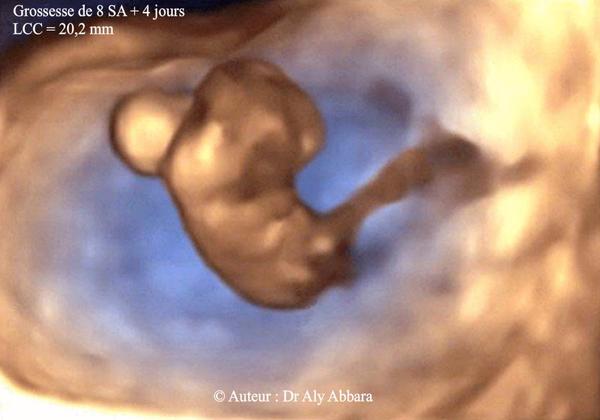

@martina_on Akurát som pozerala svoju fotku zo sona z 9tt a jediné, čo na nej vidieť je len malá fazuľka, žiadne končatiny. Ako som písala bábätko má ledva 1 cm, každý prístroj je iný a merania v takomto skorom štádiu sú úplne nepresné. V takomto týždni sa maximálne chodí len na potvrdenie akcie srdca, nič viac. Nejaké merania a kedy sa ozaj vyšetruje plod sa robí až v 12tt. Daj sa do kľudu, neviem čo to máš za lekárku, že ťa takto úplne zbytočne stresuje.

V 8 tt má sa dat rozlíšiť telíčko, ručičky a nožičky? To máš nejakú "zvláštnu" doktorku. Ja som bola v 8tt na potvrdenie bijúceho srdiečka, doktorka bola s tým spokojná a určite nič iné nehľadala

Na fotke to vyzeralo ako nejaká kukla, nič sa nedalo rozlíšiť. Ja som sa pýtala na prítomnosť manžela pri usg, a sama povedala, že až cca v 12-13tt je už možné to rozoznať,ze predtým tam proste toho veľa nevidno. Hlavne to srdiečko musí byť, aby mohla potvrdiť vitalnu graviditu.

My sme boli na sone minuly tyzden , bola som 8+6 a koncatiny sme naozaj nevideli. Vo svojom profile mam fotku, male vyzera ako cierna machula, kludne sa pozri.

Neviem aké soná máte, mali ste vy 🙂 ale moje dieťa v 8tt bolo krásne vidieť 🙂 aj s končatinami 🙂 aj prvé aj druhé 🙂 žiadna machuľa 🤷♀️

Mne v 8tt videl bijúce srdiečko a nič viac ...takže naozaj nerozumiem prečo ťa doktorka stresuje takýmto poznámkami...možno má lepšie sono ako môj doktor, to nevyvraciam samozrejme ale aj tak ...